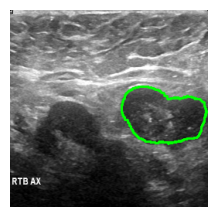

model = get_model()preds_ = get_prediction(

model=model,

model_name='wanglab/medsam-vit-base',

image=image,

boxes=[get_bounding_box(msk)],

device='cpu',

threshold=0.9

)an_img = overlay_mask_border_on_image_frm_img(image, preds_)

show_(an_img)